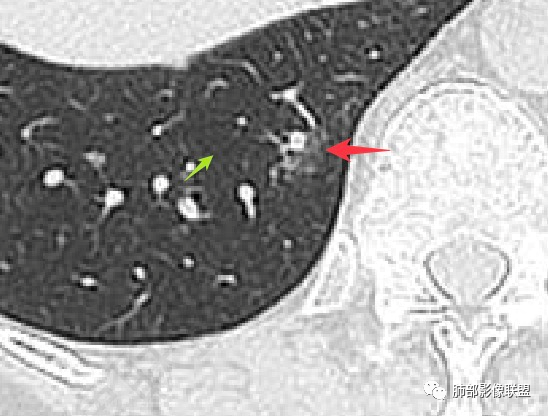

伪影太重了。仔细看,这里是两个支气管分支。而且倾向于小支气管或细支气管水平

继续看。病变的偏远端依然有支气管通行。

病变的定位,是次级肺小叶内,包绕小叶中心结构,并且有一部分病变是局限于一个腺泡结构的,也就是Reid'S小叶;

我们先分析支气管。刚才的截图是明确可以看到支气管显示的。那么它是扩张吗?

再来。注意看病灶下缘的这个支气管,这里几乎没有病灶了。与周围临近的支气管相比。